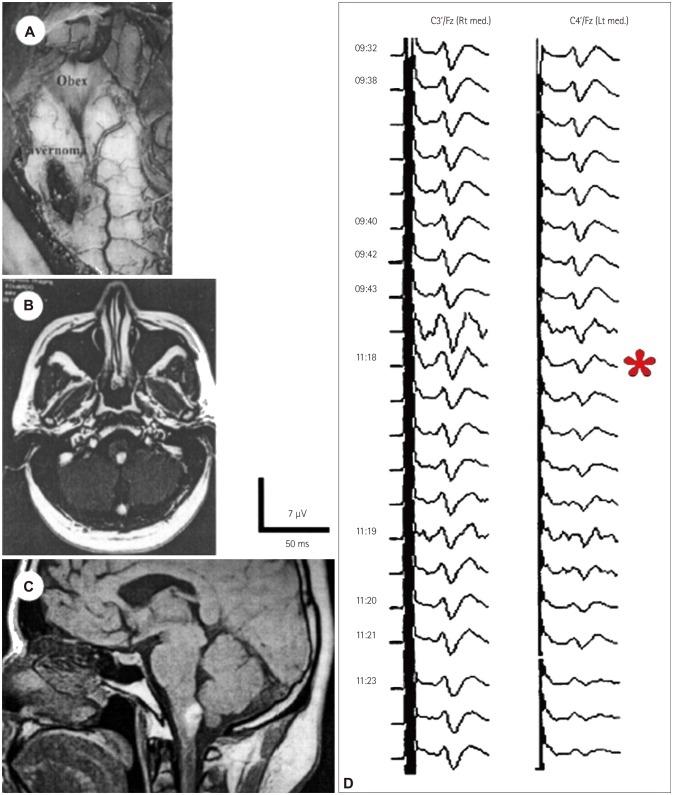

脑干功能完整性的术中监测与图谱绘制

Intraoperative Monitoring and Mapping of the Functional Integrity of the Brainstem.

在脑干及其周围进行手术干预时,医源性损伤的风险非常高。然而,手术技术和术中神经监测(ION)已经有了充分的发展,足以提高许多患者获得成功功能预后的可能性。我们对可用于脑干术中监测和定位的方法进行了批判性综述。有三类主要技术可用于评估脑干的功能完整性:1)定位,使用手持探头通过电刺激快速对神经结构进行解剖学识别;2)监测,提供有关神经组织功能完整性的实时信息;3)在手术室检查脑干反射的技术,可评估已知对大多数脑干功能至关重要的反射反应。这些反射包括已经在使用的眨眼反射,以及正在探索的其他脑干反射,如咬肌H反射。该反射仍在开发中,但可能会产生重要的功能影响。如今,有大量的ION方法可用于手术期间监测和定位脑干的功能完整性。ION方法在脑干及其周围的手术中至关重要;它们有助于切除病变,并显著改善患者的功能预后。